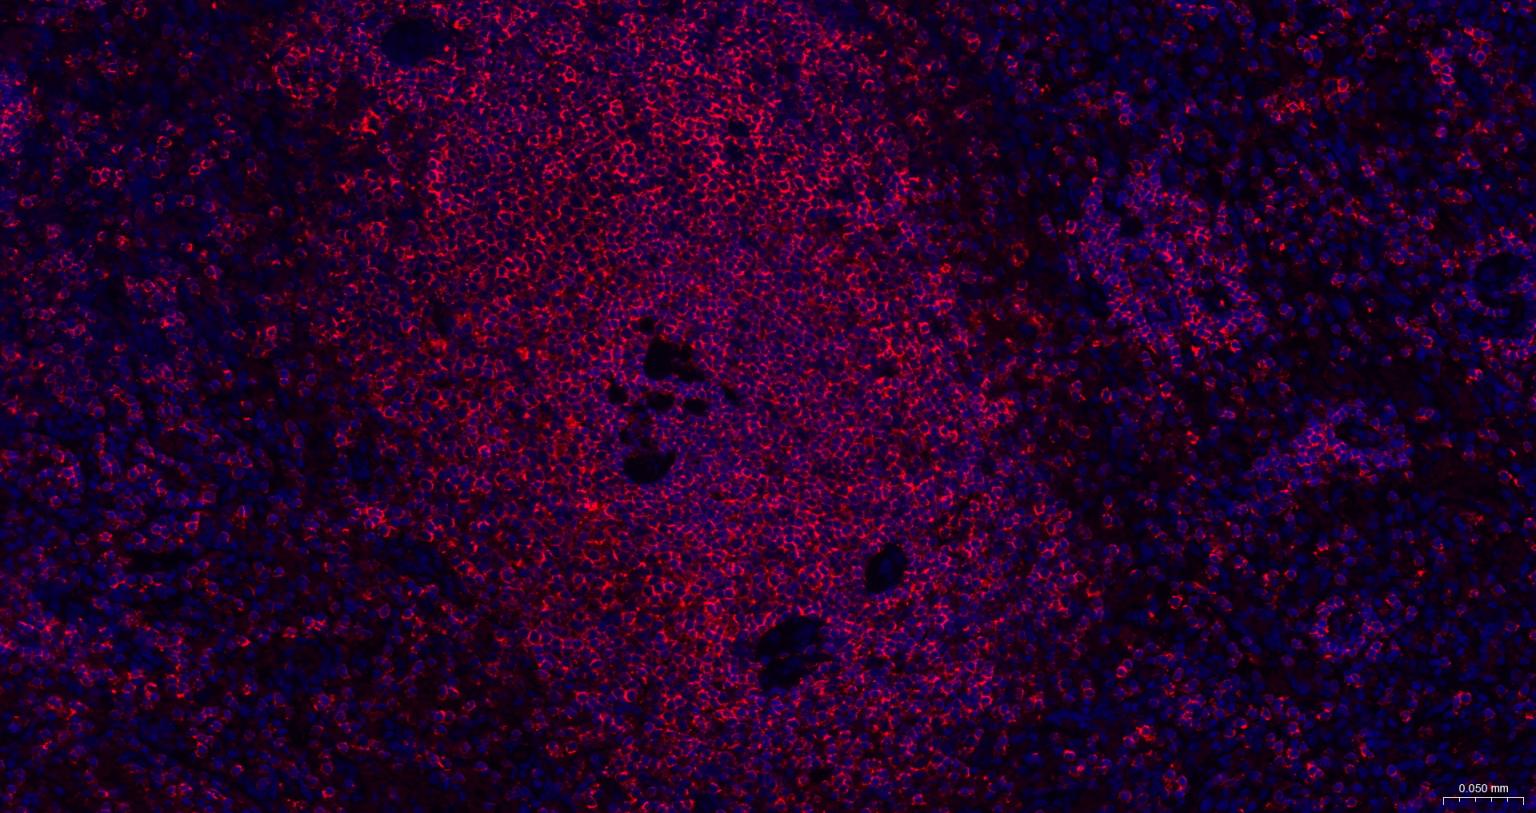

Paraformaldehyde-fixed, paraffin embedded Human Spleen; Antigen retrieval by boiling in sodium citrate buffer (pH6.0) for 15 min; The section was incubated with CD45 Polyclonal Antibody, Unconjugated (bs-0522R) at 1:200 overnight at 4°C. Followed by conjugated Goat Anti-Rabbit IgG antibody (Red, bs-0295G-BF594), DAPI (blue, C02-04002) was used to stain the cell nuclei.

Paraformaldehyde-fixed, paraffin embedded Human Tonsil; Antigen retrieval by boiling in sodium citrate buffer (pH6.0) for 15 min; The section was incubated with CD45 Polyclonal Antibody, Unconjugated (bs-0522R) at 1:200 overnight at 4°C. Followed by conjugated Goat Anti-Rabbit IgG antibody (Red, bs-0295G-BF594), DAPI (blue, C02-04002) was used to stain the cell nuclei.